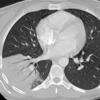

Case 14 RLL pneum CT

Date: 04/17/2005

Views: 5025